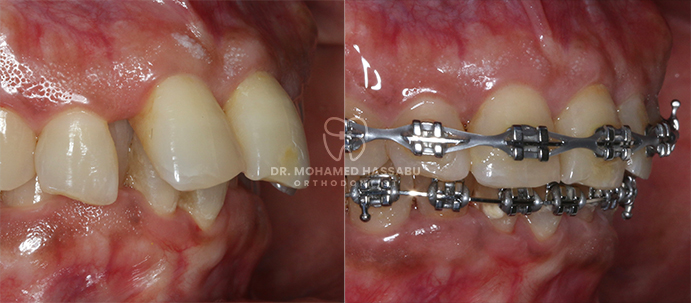

Specialized Braces:

We offer a range of specialized braces that are designed to be comfortable and effective. Our team of Orthodontists in Dubai will explain the different types of available braces and recommend the most suitable option for your child.